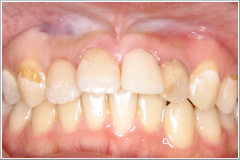

正月気分間覚めやらぬ1月8日、「前歯が折れてしまって、成人式に出られないんです。何とかならないでしょうか?」 という電話がありました。晴れの舞台に“歯っ欠け”ではさすがに気の毒で、「仮歯くらいなら、なんとかなりますよ」と答え、来院してもらうことになりました。その患者さんは20歳の女性(Cさん)で、左の写真の様なお口の状態でした。